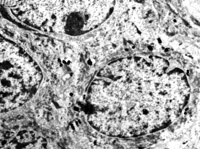

5-2-8 傷后第10天,皮膚附件上皮細(xì)胞成簇分布,核仁邊集,內(nèi)質(zhì)網(wǎng)擴(kuò)張,胞質(zhì)內(nèi)含較多張力原纖維  TEM×6000

5-2-13 愈后:表皮與真皮之間完整的真皮-表皮連接  TEM X 8000

5-2-14 愈后新生皮膚真皮內(nèi)纖維細(xì)胞呈常態(tài),膠原纖維粗細(xì)均勻,排列有序,達(dá)生理性愈合  TEM×10000